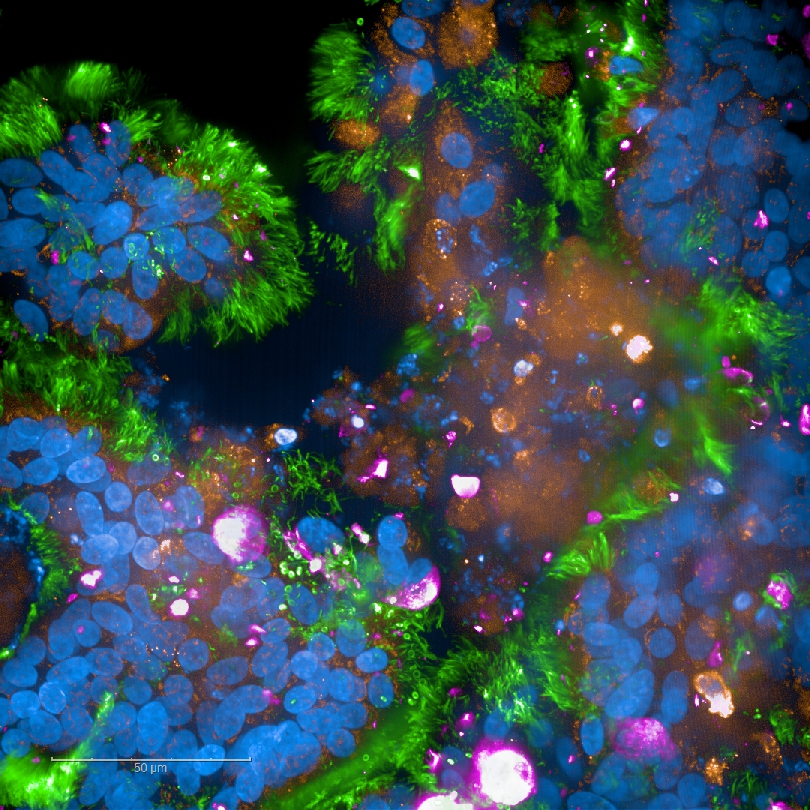

Highly differentiated cell culture models are also being developed by Wilflingseder’s group, in order to allow research into the initial interactions between various pathogens (HIV-1, Aspergillus, Chlamydia) in the acute phase of infection. The established human 3D mucous membrane model is very promising in this context. The in vitro system allows detailed analyses of HIV-1 and HIV-2 with molecules and enzymes of an intact, complex mucous membrane and the development of novel therapeutic approaches. The mucosal/immune model is funded with a grant from the National Institutes of Health (NIH). Together with our American colleague, Thomas J. Hope from Northwestern University in Chicago, the behaviour of HIV-neutralising antibodies in this human mucosal model will be investigated, in order to pave the way for new vaccination strategies against HIV.

The respiratory barrier/immune model has been optimised in recent years as part of an ÖNB project. This 3D model and differentiated apical-out lung organoids are applied in further studies using pathogenic fungi (in cooperation with CL-F.) or SARS-CoV-2 (project leader: WP > COVID19 project).

- Chandorkar P, Posch W, Zaderer V, Blatzer M, Steger M, Ammann CG, Binder U, Hermann M, Hörtnagl P, Lass-Flörl C, Wilflingseder D: Fast-track development of an in vitro 3D lung/immune cell model to study Aspergillus Sci Rep. doi: 10.1038/s41598-017-11271-4. 2017 Sep 14;7(1):11644.